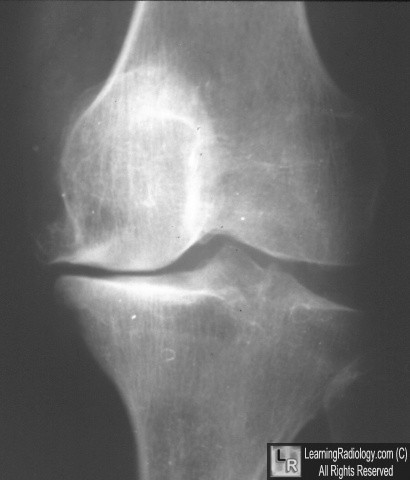

Radiographic signs in knee of decreased MEDIAL joint space with lateral space preserved

DJD of Knee